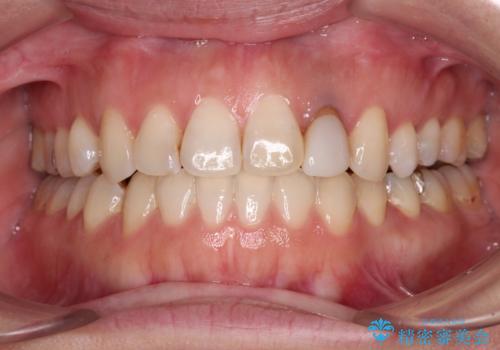

開咬と変色した前歯 インビザライン矯正とオールセラミッククラウン治療

- 前歯の開咬と失活により変色した前歯を気にして来院された患者様です。

開咬の治療は、前歯を閉じるように引っ張り出すよりも、上下臼歯を圧下(骨内にめり込ませる)させることで進める方が長期的に安定した歯列を維持できます。

インビザラインは臼歯の圧下を効果的に行えるため、インビザラインを用いて矯正治療を行うこととしました。

矯正治療が概ね終了した時点で前歯をオールセラミッククラウンにて補綴治療を行い、その後インビザラインにて細かい部分を仕上げていくことしました。